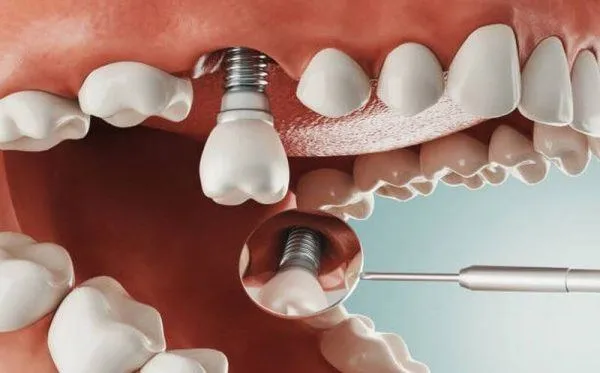

Khi trồng răng implant, vị trí đặt implant phụ thuộc vào kích thước xương hiện có. Cùng với đó là nhu cầu của người bệnh cũng như